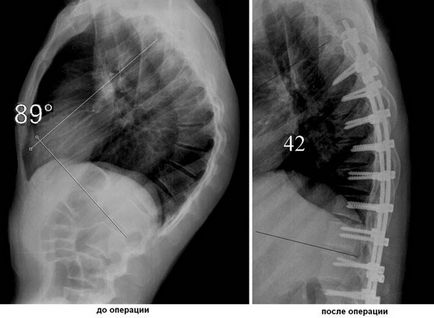

sebészi kezelés

Ha konzervatív kezelési módszerek is tehetetlen, és a betegség továbbra is folyamatban van, nem vették igénybe a műtét a kyphosis. Javallatok sebészet visszaállítani a görbület a gerinc:

- harmadik fokozatot kyphosis, amikor a szög görbületi a gerincvelő rúd több mint 60 °;

- Konzervatív kezelés nem ad meg a kívánt eredményt hosszú ideig;

- vényköteles gyógyszerek nem segítenek megszabadulni a fájdalomtól;

- hibás munka a kismedencei szervek;

- gerincvelő-kompresszió;

- izomsorvadás.